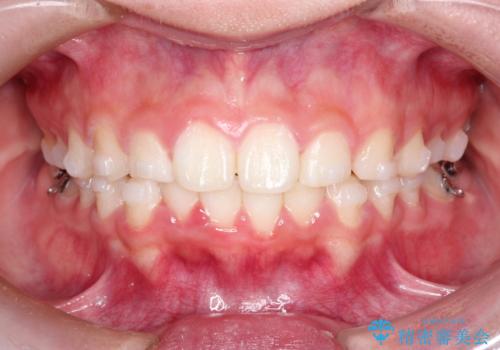

【インビザライン】出っ歯を引っ込めたい。

- 前歯の隙間と、出っ歯に見えることを主訴に来院されました。

できるだけ目立たない装置をご希望されましたので、インビザラインにて治療を行いました。

治療中は、できるだけ前歯を下げることができるように”顎間ゴム”を使用します。

”顎間ゴム”を利用することで、奥歯を後ろに動かす力を強めることができます。